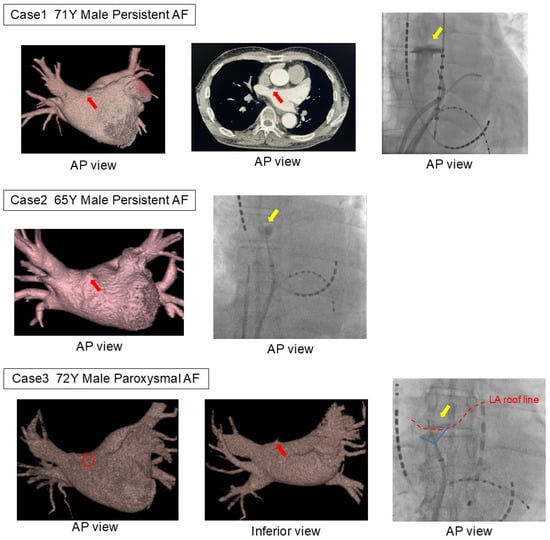

The locations and frequencies of the LADs are presented in Figure 1. LADs were identified at various sites within the left atrium, with the anterosuperior aspect of the septum or anterior region of the right superior pulmonary vein representing the most common locations, accounting for 53.4% of the cases across the 16 segments. The anterior region of the left superior pulmonary vein was the second most frequent site, observed in 15% of cases.

Figure 1. Locations and frequencies of LADs. This figure shows the distribution of LADs in the left atrium in 595 cases. The left side of the figure represents the medial left atrium, and the top represents the superior aspect. The most common location was the anterosuperior aspect of the septum, on the anterior side of the right superior pulmonary vein, followed by the anterior side of the left superior pulmonary vein. LAD, left atrial diverticulum; RSPV, right superior pulmonary vein; RIPV, right inferior pulmonary vein; LSPV, left superior pulmonary vein; LIPV, left inferior pulmonary vein.